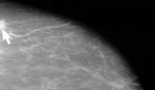

SABCS 2014

The 2014 San Antonio Breast Cancer Symposium is presented by the Cancer Therapy & Research Center at UT Health Science Center San Antonio, the American Association for Cancer Research, and Baylor College of Medicine. The driving force behind this collaboration is the shared mission of the organisations to advance progress against breast cancer. As exciting strides are made in the field of breast cancer research and treatment our program continues to present essential up-to-the minute information combined with engrossing discussion for basic, translational and clinical cancer research professionals.